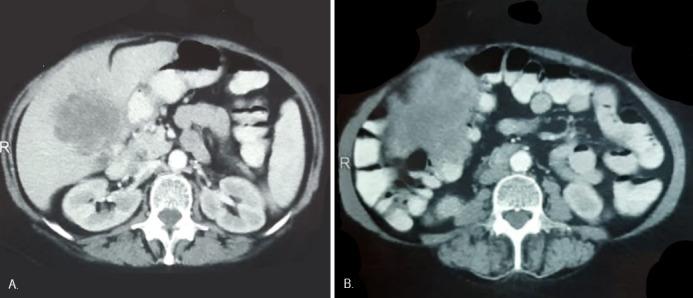

Cholecystocolonic fistula (CCF) is the second most common cholecystoenteric fistula, associated in most cases with stone disease. Symptoms are usually minimal or nonspecific, and preoperative diagnosis is uncommon. Although the incidence of FCC caused by gallbladder cancer comprises 1.7% of cases, it is necessary to suspect it in order to adopt the best therapeutic strategy.

胆囊结肠瘘(CCF)是第二常见的胆囊肠瘘,多数情况下与结石病相关。症状通常轻微或不具特异性,术前诊断并不常见。尽管胆囊癌导致的胆囊结肠瘘发病率占病例的1.7%,但为了采取最佳治疗策略,仍有必要怀疑此病。